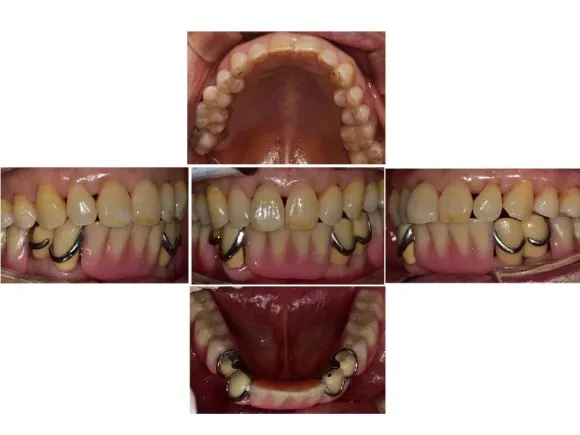

부분틀니 장착 후

완성하였지만 이렇게 웃을 때 고리가 보이게 되어 심미성을 위해 한 번 더 제작하게 되었습니다.

부분틀니 장착 후 / 틀니 고리 내리기 전

부분틀니 장착 후 / 틀니 고리 내린 후

최종으로 마무리된 후 사진입니다.

웃을 때 보이던 고리가 사라져 웃었을 때 깨끗한 모습으로 수정되었습니다.